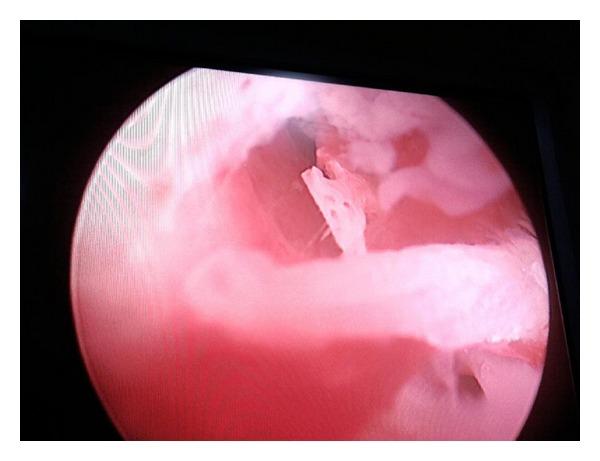

First trimester abortion: a rare cause of intrauterine bony spicules.

Bony fragments in the uterus occur after second trimester termination of pregnancy following retained fetal bones. Very rarely, they can form following first trimester loss. Clinical symptoms range from pain, menstrual symptoms, and infertility. Ultrasound shows a hyperechoic shadow, and treatment is by curettage or hysteroscopic removal.